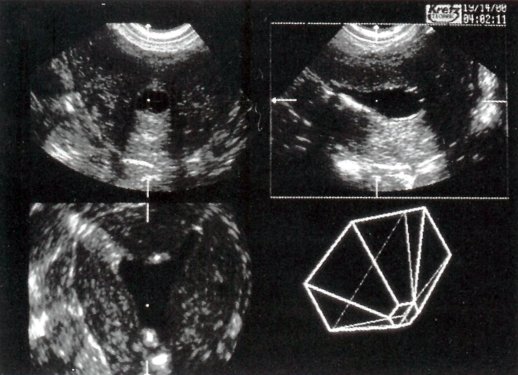

Рис. 2. Обычная трансвагинальная эхограмма (а) обнаруживает два отдельных внутриматочных эхосигнала, что позволяет предположить наличие двурогой матки или матки с перегородкой. Венечный срез (слева внизу), полученный с помощью трехмерной ультрасонографии (б), выявляет только минимальную выпуклость верхней части полости матки, что свидетельствует о дугообразной матке, клинически незначительной небольшой аномалии.

Мы обследовали женщин с разнообразными пороками развития матки с помощью трехмерного ТВУЗИ, и в некоторых случаях - трехмерной соногистерографии. Эти пороки развития включали в себя: DES матку, дугообразную, с полной или неполной перегородкой, двурогую матку с перегородкой влагалища (в одном случае - с гемивагиной). Мы также установили случай эктопической грыжи устья мочеточника, сообщавшейся с кистами протока Гартнера. ЯМР и операционные данные хорошо коррелировали с результатами трехмерного УЗИ. При дугообразной матке трехмерный ультразвук помог достоверно исключить двурогую матку или матку с перегородкой, которая была заподозрена при двухмерном УЗИ.